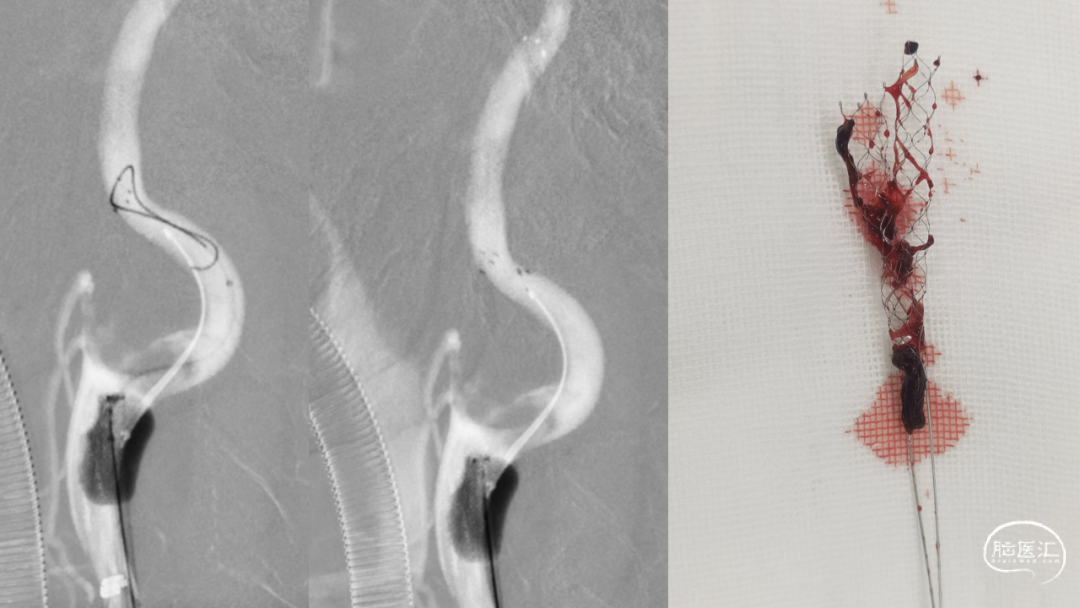

取之有道·第54期|李子付:Flowgate2取栓应用

看李子付解“取之有道”

滑动浏览更多内容